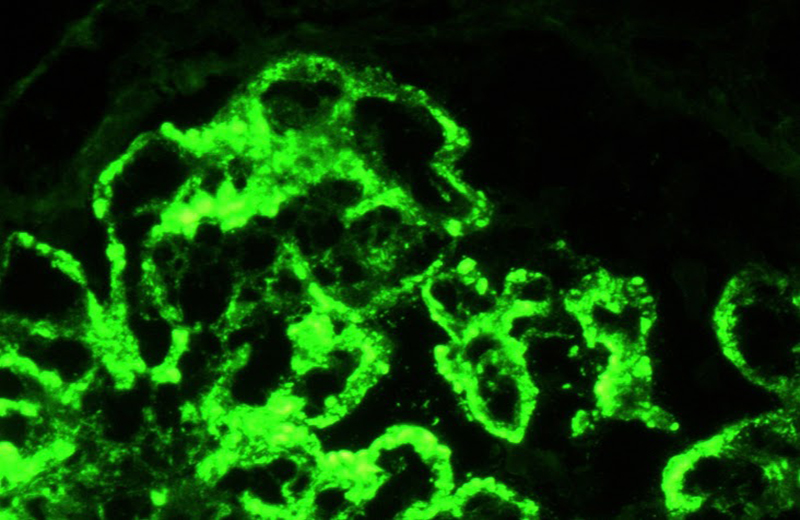

NefropatĂa lĂşpica clase IV. Inmunofluorescencia directa contra la cadena ligera lambda. Se observan inmunocomplejos epimembranosos, subendoteliales y mesangiales.

Foto: Dra. Norma Uribe (INCMNSZ)